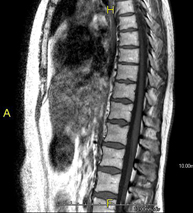

Prueba diagnóstica no invasiva que consiste en la obtención de imágenes de alta definición anatómica de la columna cervical mediante el empleo de un campo electromagnético y ondas de radio (con un emisor y un receptor). No utiliza radiación ionizante. Indicaciones: traumatismo, degeneración de la columna, hernias. - RM Columna dorsal

Prueba diagnóstica no invasiva que consiste en la obtención de imágenes de alta definición anatómica de la columna dorsal, mediante el empleo de un campo electromagnético y ondas de radio (con un emisor y un receptor). No utiliza radiación ionizante. Indicaciones: traumatismo, problemas degenerativos, hernias, tumores. - RM Columna lumbar